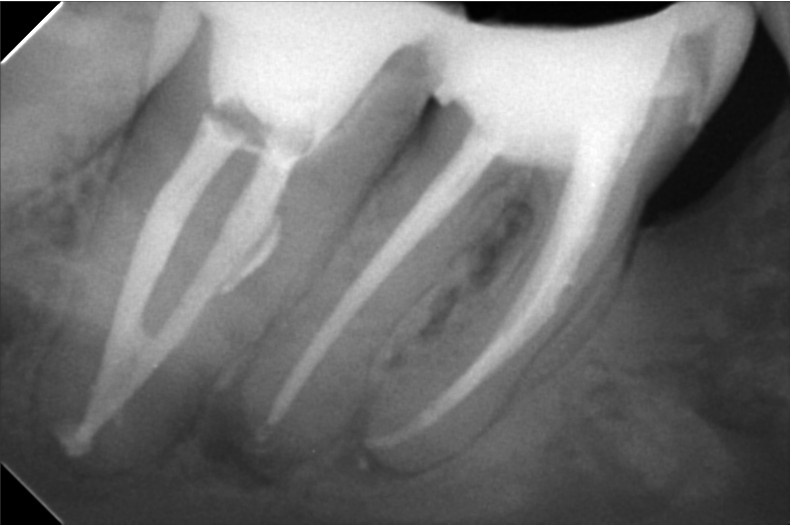

علاج الجذور يعد فرع من فروع طب الأسنان الذي يعمل على معالجة مشكلات الجذور التي تساعد على توفير الحماية والتغذية داخل الأسنان من التعرض لأي عوامل خارجية مثل: الأطعمة الساخنة والباردة هناك العديد من التقنيات التي ساعدت في علاج الجذور و التي توفرها مركز أوبال للأسنان, ومنها:جهاز الاشعة الثلاثية الابعاد , جهاز الميكروسكوب, أدوات تنظيف القنوات العصبية واخيرا حشو القنوات العصبية فكل منها لها دور مهم في عملية علاج الجذور فالاشعة الثلاثية الأبعاد تساعد في رسم خريطة دقيقة للقنوات العصبية أما الميكروسكوب فهو يعمل على توضيح الرؤية, تتيح أدوات تنظيف القنوات العصبية لأول مرة التعامل مع القنوات الضيقة والملتوية بشدة وتعد حشو القنوات العصبية عن طريق الحقن من أحدث التقنيات الطبية التي تضمن نجاح نجاح علاج الجذور أصعب الحالات من الجلسة الأولى فهي تعمل على إحكام غلق القنوات الأساسية وخصوصا الفرعية والتأكد من انها خالية من البكتيريا.